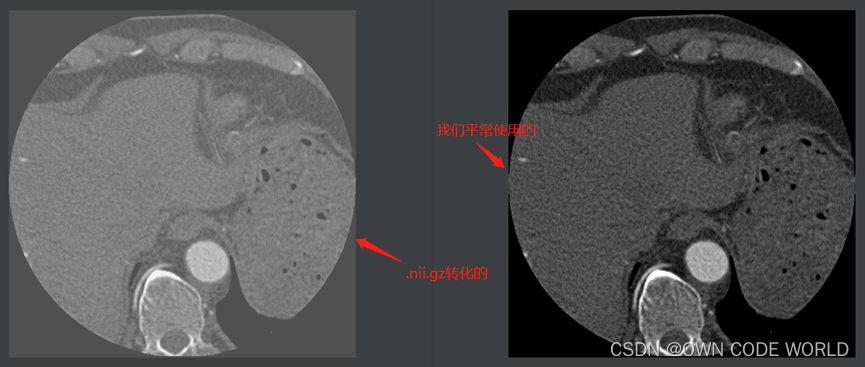

17.在这个模型中,测试出来的结果为下图.nii.gz格式的,因此我们可以使用ITK-SNAP软件来查看。

下面时使用ITK-SNAP软件来查看的结果图:

Img.nii.gz

pre.nii.gz

Img.nii.gz+ pre.nii.gz

Img.nii.gz+ gt.nii.gz

因为这组数据的dice有86%,所以效果还不错。

19.由于我们以前使用的模型比如unet,跑出来的结果都是png,但是此为.nii.gz,因此下面时想将.nii.gz转化为png.因此就去查找了相关的代码,并进行了简单的修改。将.nii.gz 转化为了png格式,如下图所示,转化过来的png存在一些问题(Q5:猜测是像素值的区间出现了问题,例如边缘部分的像素值本来是0,但是现在是80.这个问题还未解决)